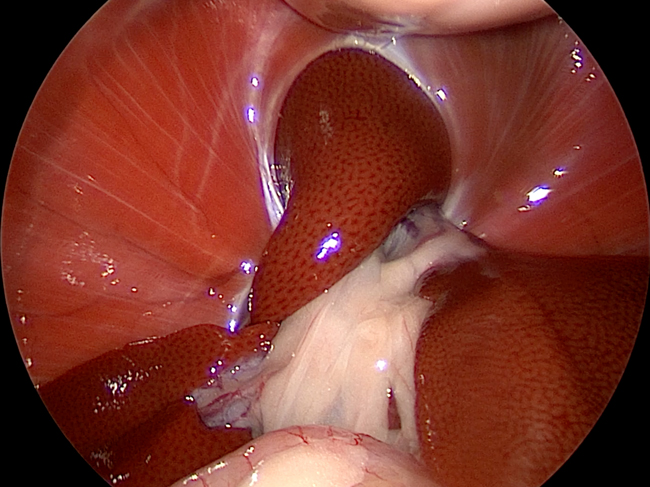

手術の様子

左:腹腔鏡下での逸脱臓器の確認